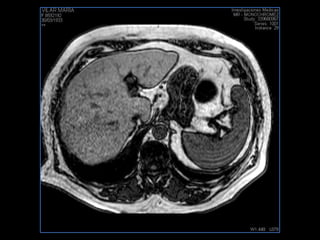

PROTOCOLO hígado graso AXIAL in phase y out phase AX T1 y AX fat sat +SAG T2  CON   GADOLINIO :  COR T1+AX T1(DIN) SAT: NO  FASE: RL THK: 4MM  COIL:  GAP: (FACTOR 1.4)  FOV: 40 CM NEX:2 SINCRONIZACION RESPIRATORIA EN 3 O 4 CICLOS ALE

PROTOCOLO hemocromatosis AXIAL supresión grasa /AX multieco en higado COR T2 AX T1 +SAG T2  CON   GADOLINIO :  COR T1+AX T1 SAT: NO  FASE: RL THK: 4MM  COIL:  GAP: (FACTOR 1.4) 1MM FOV: 40 CM NEX:2 SINCRONIZACION RESPIRATORIA EN 3 O 4 CICLOS ALE